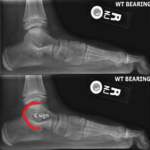

[doctormodu]2 talocalcaneal coalition C-sign X-ray

06 거종골 유합 Talocalcaneal Coalition